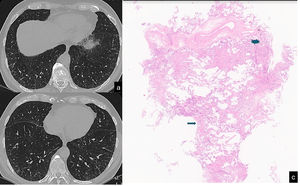

The UIP pattern represents the final step of the ageing process following maladaptive repair that induces alterations in both the airway cellular composition and function. Therefore, if the healthy distal airway epithelium is composed primarily of mucus-producing and multiciliated cell populations, patients with IPF show misexpression of mucus and aberrant ciliation. Consequently, these patients show increased wall thickness and architectural distortion of the distal airways on multidetector CT scans, which can be more precisely visualised on micro-CT images. Micro-CT scans of the explanted lungs of patients with IPF show dramatic loss of the terminal bronchioles and a significant decrease in the alveolar surface.136 Repeated aberrant attempts at regeneration of the terminal airways through the activation of developmental pathways result in honeycomb cysts.113 The stereological analysis of HC has confirmed its spatial relationship with small conducting airways. The corresponding multidetector CT findings include an increase in the number and degree of distorted airways in the 14th to 17th generation.137 Another macroscopic consequence of this metaplastic lining process the progressive bronchiolisation of the periphery of the lungs, with traction bronchiectasis beginning to appear beneath the pleura and, over the course of the remodelling, tending to assume the aspect of HC over a continuum of aberrant lung remodelling.138 Moreover due to the large and scarcely flexible space incapable of gas exchange, another immediate consequence is the loss of elastic recoil and the collapse of HC during the maximal expiration, which has been documented by CT expiratory scans (Fig. 5).

Inspiratory (a,c) and espiratory CT scan (b,d) shows UIP pattern characterized by the presence of honeycombing in the anterior segment of the left upper lobe, traction bronchiectasis and focal fibrotic ground glass in the left lower lobe. A mild peripheral reticulation is also present in the right lung parenchyma. The expiratory scan (b,c) shows a homogenous reduction in lung volumes associated with a diffuse increase of the lung density, in absence of air trapping. Interestingly, the area of honeycombing doesn't collapes (red ellipse). Moreover, the focal ground glass surrounding traction bronchiectasis, shows a lack of traction bronchiectasis collapse (red arrow).